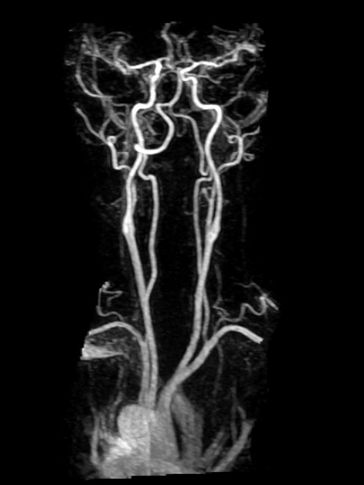

MRI Brain + Brain & Neck Angiogram

Cerebral aneurysms, brain tumors, stroke, dizziness, slurred speech, etc.